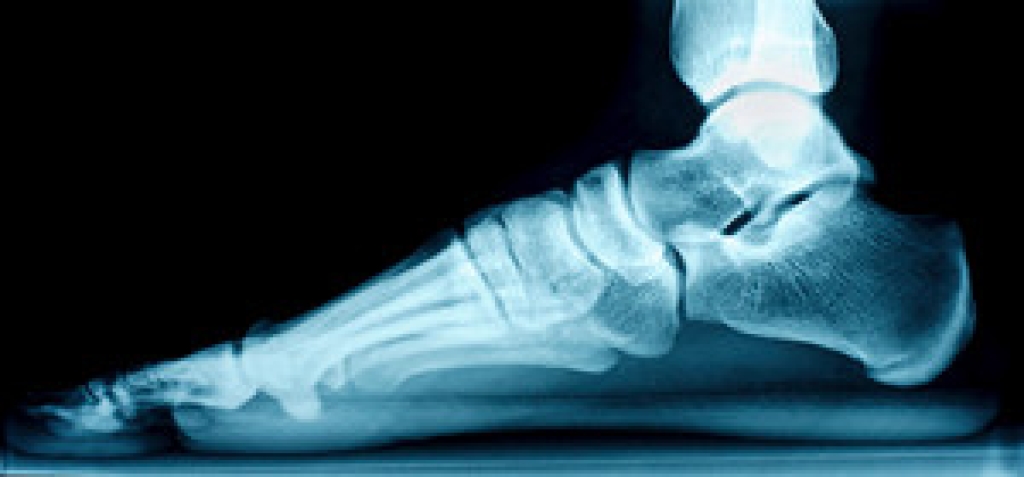

Your podiatrist will diagnose your bunion by doing a thorough examination of your foot. He or she may also conduct an x-ray to determine the cause of the bunion and its severity.